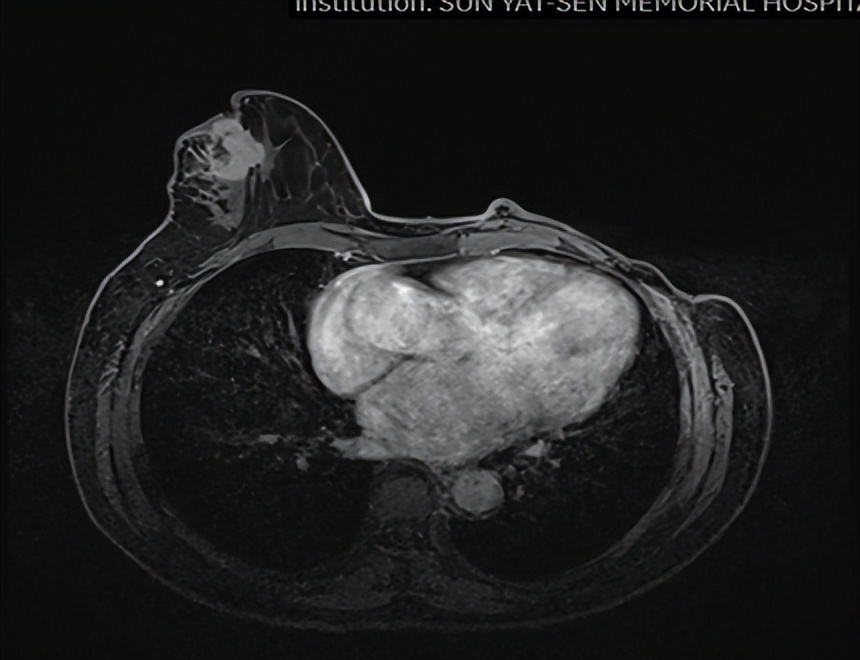

乳腺MR

右侧乳头后侧中部多个异常信号结节(较大者23*15mm),符合乳腺癌,BIRADS:5类。右侧腋下肿大淋巴结,考虑转移。